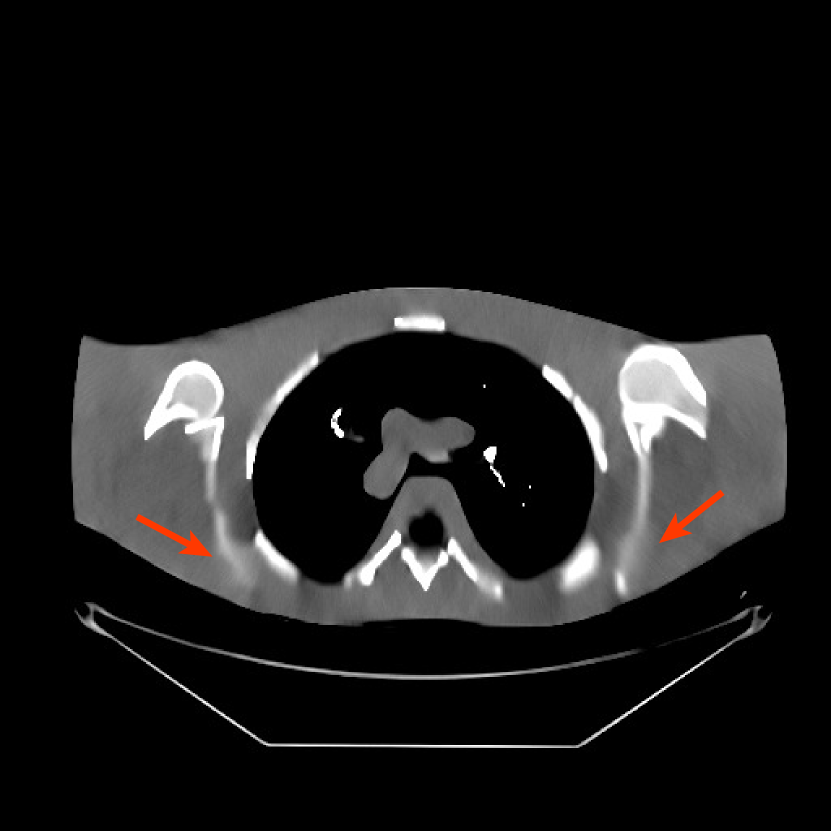

We used the pre-learned union of 15 square transforms from the XCAT phantom simulations to reconstruct the synthesized helical chest scan volume of size 420×420×222420420222{420\times 420\times 222} with Δx=Δy=1.1667subscriptΔ𝑥subscriptΔ𝑦1.1667\Delta_{x}=\Delta_{y}=1.1667 mm and Δz=0.625subscriptΔ𝑧0.625{\Delta_{z}=0.625} mm. The sinograms were of size 888×64×3611888643611888\times 64\times 3611. Since the clinical data is synthesized via the PWLS-ULTRA reconstruction, the noise model for this synthesized data is obscure, making it difficult to determine appropriate low-dose levels for such data. We tested the radiation dose of I0=1×104subscript𝐼01superscript104I_{0}=1\times 10^{4} with an electronic noise variance the same as the XCAT phantom simulation, i.e., σ2=25superscript𝜎225\sigma^{2}=25. The percentage of non-positive pre-log measurements for the synthesized clinical data in this case was around 0.14%percent0.140.14\%. Such non-positive values were replaced by 1×1051superscript1051\times 10^{-5} for PWLS-based methods. Fig. 8(a) shows the “true” clinical image that was reconstructed from real clinical regular-dose sinogram using the PWLS-ULTRA method.

Similar to the XCAT phantom simulation, the initial image for both SPULTRA and PWLS-ULTRA was a reconstruction obtained using PWLS-EP. We set the regularizer parameter βepsubscript𝛽𝑒𝑝\beta_{ep} for PWLS-EP to 215superscript2152^{15} to generate a smoother (with less noise) initial image, which led to good visual image equality for the SPULTRA and PWLS-ULTRA reconstructions. Since the optimization problem for PWLS-EP is strictly convex, we simply initialized PWLS-EP with a zero image. Fig. 8(b) shows the PWLS-EP reconstructed image for I0=1×104subscript𝐼01superscript104I_{0}=1\times 10^{4}. We set the regularizer parameters for both PWLS-ULTRA and SPULTRA as γc=5×104subscript𝛾𝑐5superscript104\gamma_{c}=5\times 10^{-4}, and β=1.5×104𝛽1.5superscript104\beta=1.5\times 10^{4}.

V-B2 Reconstruction results for the synthesized clinical data

Fig. 9 shows three axial slices from the 3D reconstructions with SPULTRA and PWLS-ULTRA at I0=1×104subscript𝐼01superscript104I_{0}=1\times 10^{4}: the middle slice (No. 67) and two slices located farther away from the center (No. 90 and No. 120). The image profiles along a horizontal line (shown in green) in the displayed slices are also shown in Fig. 9. The reconstructed slices using PWLS-ULTRA appear darker around the center compared to the “true” clinical image and the reconstructions with SPULTRA. This means PWLS-ULTRA produces a strong bias in the reconstruction. The bias can be observed more clearly in the profile plots: the pixel intensities for the SPULTRA reconstruction better follow those of the “true” clinical image, while those for the PWLS-ULTRA reconstruction are much worse than the “true” values. Moreover, SPULTRA achieves sharper rising and failing edges compared to PWLS-ULTRA. In other words, SPULTRA also achieves better resolution than PWLS-ULTRA. Fig. 9 also shows a zoomed-in ROI for each of the chosen slices, and highlights some small details with arrows. It is clear that in addition to reducing the bias, SPULTRA reconstructs image details better than PWLS-ULTRA.